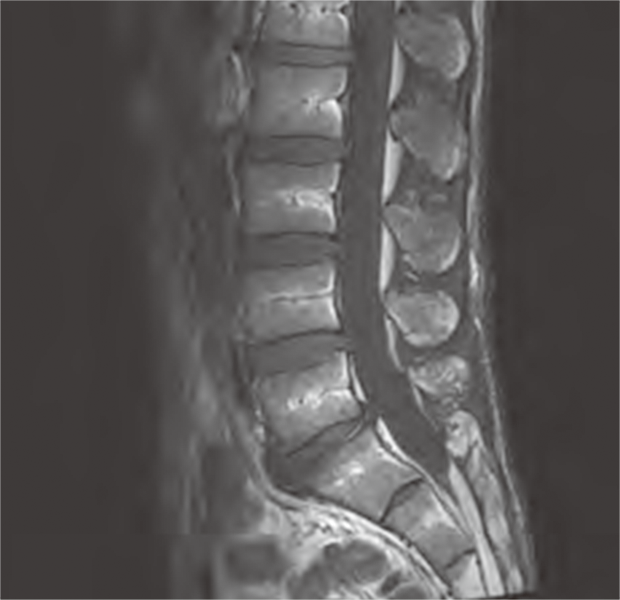

MRI検査とは強力な磁石と電波を利用することで体内の臓器や組織を画像化する検査法です。この検査では磁石の力や電波を使用しての検査なので放射線による被ばくはありません。当院では現在1.5T装置と3.0T装置が1台ずつで検査を行っています。このT(テスラ)は磁束密度の単位です。強い磁石ほど値が大きくなります。

3.0T装置では1.5T装置と比較し、磁石の力が強いのでよりきれいな画像を得ることができるため血管や神経、細かい場所を検査するのに適しています。しかし、体内の金属や体の構造による画像への影響は1.5T装置の方が3.0T装置よりも抑えられる場合があります。また、磁石の力が強いほど体への影響も大きく年齢や体格、妊娠の有無、手術歴などによって制限を受ける場合もあります。そのため、当院では検査の目的や患者さんの状態に合わせて1.5Tの装置と3.0Tの装置を使い分けて検査を行っています。